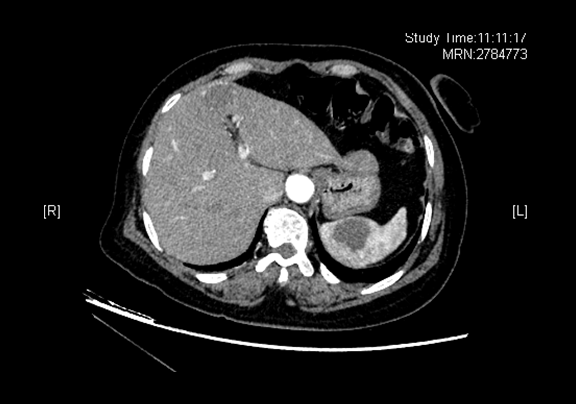

术前CT检查:

动脉期

全腹CT 肝左叶内略低密度灶,脾脏内略低密度灶

将0.625mm双源薄层CT资料的静脉期和动脉期Dicom格式文件导入海信CAS系统。

通过调节窗宽窗位调整CT序号,对肿瘤,肝实质,胆囊,下腔静脉,肿瘤,肝动脉、门静脉及肝静脉等进行三维重建;系统自动计算肿瘤体积和肝脏体积。